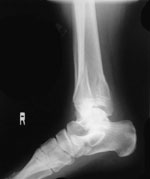

レントゲン写真を読影した医師の判断にて治癒とした (図5)。

受傷後88日後レントゲン正面像。 |

|

受傷後88日後レントゲン側面像。 |

右脛骨・腓骨ともに骨折部の癒合は良好であり、画像写真においてまったく問題がないことが確認できた。このことは徒手整復術が適応であったことを裏付ける結果であったと考えている。日常生活動作に支障が見られないことから、後療法が適切に行うことができたと認識している。